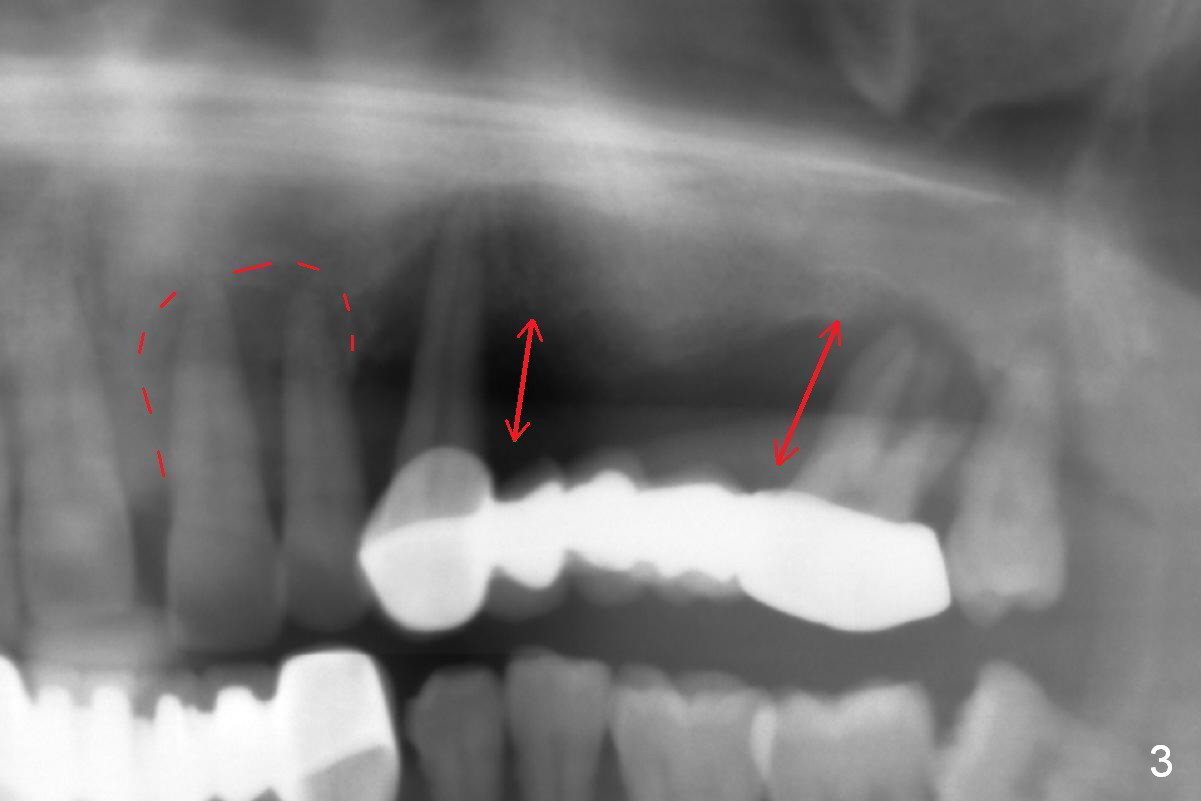

A 45-year-old man has advanced periodontitis and bruxism (sufficient remaining bone height, Fig.1). Full mouth restoration will be done by quadrant with preservation of a few of relatively healthy teeth. The 1st quadrant to be treated will be the upper left (Fig.2). The teeth #9-11 and 15 will be extracted (Metronidazole) with immediate implants. A delayed implant will be added at #13 for #11-15 bridge (Fig.4). In addition to the large radiolucency around the roots of #9 and 10 (Fig.3 red dashed line), the gingiva at #11 and 15 is excessively thick (red arrows). For example at #11, a long implant has to be placed a little more outside the bone (Fig.4 green area), since the longest cuff of the abutment (red area) is 5 mm for UF implant system. The longer the cuff, the less amount of the implant will be outside the bone with less chance of periimplantitis. When the coronal implant threads are exposed, a large amount of bone graft has to be placed (Fig.4 yellow circles).